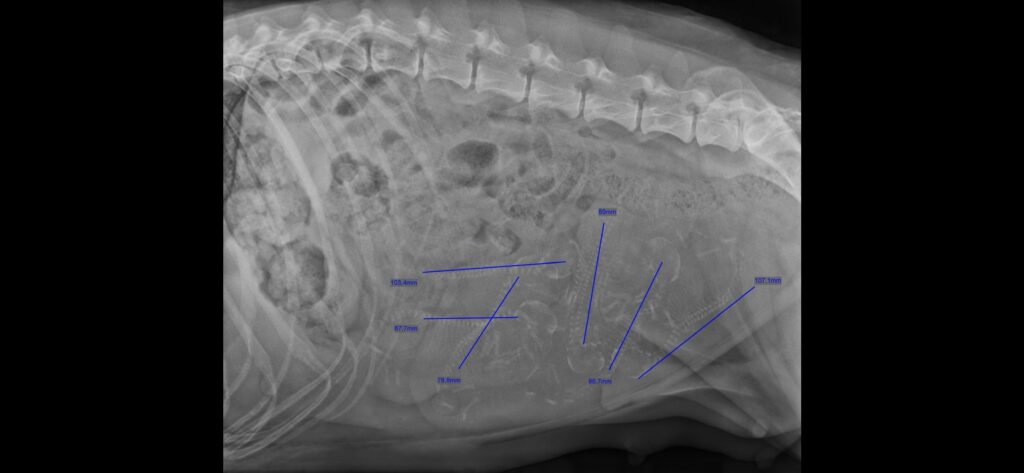

Veterinären säger sig se 6 st valpar i magen. Hur många ser du?